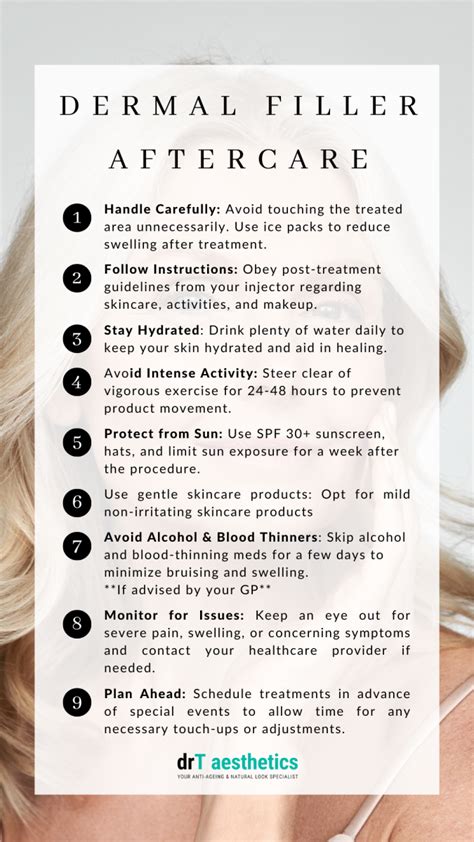

Potential Complications and Risk Management

While preauricular region filler placement is generally safe, practitioners must remain vigilant about potential complications:

- Vascular occlusion risks

- Potential nerve irritation

- Asymmetry or uneven product distribution

Comprehensive understanding of facial vasculature and precise injection techniques can significantly mitigate these risks.

Most hyaluronic acid-based fillers in this region last approximately 9-12 months, depending on individual metabolism and product characteristics.

Most patients experience minimal discomfort. Topical anesthetics are typically applied before the procedure to enhance patient comfort.

Potential risks include temporary swelling, bruising, asymmetry, and rare complications like vascular occlusion. Choosing an experienced practitioner minimizes these risks.